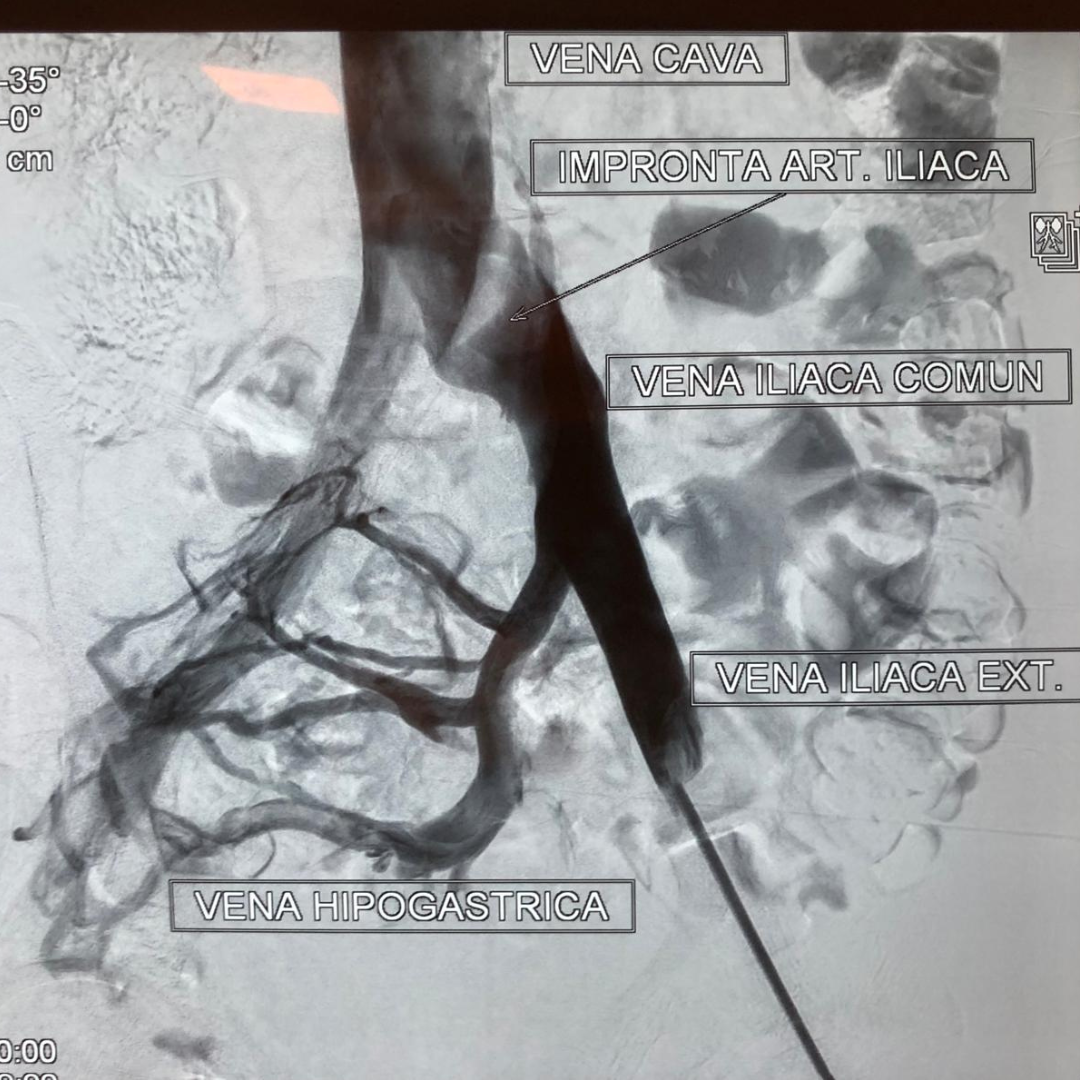

Antes: Oclusión bilateral ilíaca

Antes

Oclusión de ambas venas ilíacas/Sindrome de congestión pélvica

Después: Reconstrucción con stents

Después

Reconstrucción con stents. Flujo normalizado y resolución clínica.